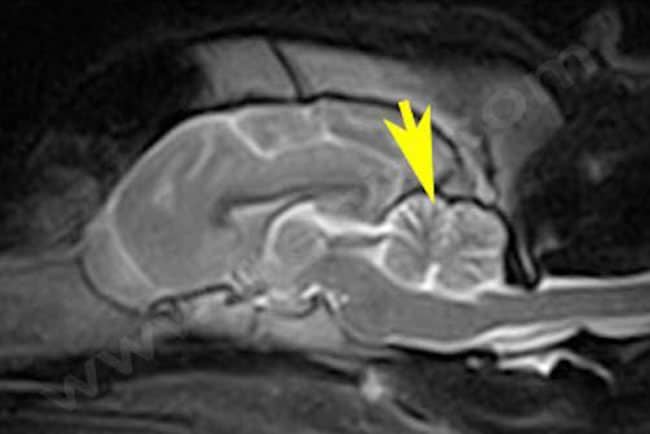

Le diagnostic se fait généralement à occasion d’une consultation specialisée de neurologie, par exclusion d’autres affections cérébelleuses (inflammatoires, malformations) et par confirmation d’une atrophie du cervelet en réalisant une résonance magnétique (IRM).